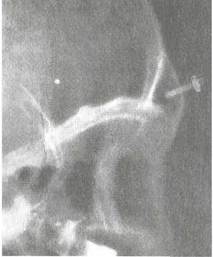

Рентгенологическое исследование в прямой и боковой проекциях и КТ — наиболее информативные методы исследования, позволяющие оценить объем и глубину пазух, выявить в них гнойный процесс. В затруднительных случаях с диагностической целью производят трепанопункцию лобной пазухи.

При наличии гнойного процесса, подтвержденного рентгенологическими исследованиями или данными КТ, необходимо зондирование лобной пазухи специальной изогнутой канюлей или трепанопунщия лобной пазухи. Зондирование удается не всегда из-за извитости канала лобной пазухи, гиперплазиро-ванного крючковидного отростка, увеличенного большого решетчатого пузырька и др.

Поэтому трепанопунщия лобной пазухи в настоящее время остается наиболее эффективным методом эвакуации гнойного содержимого из лобной пазухи.

Прибор для трепанопункции (М.Е. Антонюк) состоит из сверел, устройства, обеспечивающего ручное вращение сверла и ограничение его проникновения в глубину тканей, набора специальных канюль для фиксации в отверстии и промывания пазухи. Перед операцией производят разметку для определения точки трепанопункции: проводят вертикальную срединную линию по центру лба и спинке носа, вторую линию проводят горизонтально перпендикулярно к первой по костному краю надбровной дуги, третья линия является биссектрисой прямого угла между первой и второй линиями. Отступя на 1 — 1,5 см от угла отмечают точку для наложения трепанобора (рис. 2.27). При этом обязательна корректировка положения и глубины пазухи по прямой и профильной рентгенограммам.

Рис. 2.28. Рентгенограмма в боковой проекции. Положение канюли в лобной пазухе после трепанопункции.

ты в течение 2—7 дней. В некоторых случаях после трепано-пункции контролируют положение канюли в пазухе по рентгенограмме в боковой проекции (рис. 2.28).